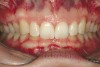

Figure 2a  Corticotomy SFOT. The patient presented with unesthetic anterior bridgework that was placed at age 14 to compensate for congenitally missing Nos. 7 and 10.

Figure 2a

Figure 2b  A corticotomy in SFOT is a surgical technique in which only the cortical bone is cut, perforated, or mechanically altered to the depth of the medullary bone and the medullary bone remains intact.

Figure 2b

Figure 2c  One week postsurgery with mesial buildups on Nos. 5 and 12 and thin pontics on archwire to conceal spaces during closure.

Figure 2c

Figure 2d  Prerestorative orthodontics was completed in 5 months. Final result 3 years, 4 months after completion.

Figure 2d

Figure 2e  Teeth Nos. 5 and 12 were converted to Nos. 6 and 11, and Nos. 6 and 11 were converted to Nos. 7 and 10. Nos. 4 and 13 were enlarged. Note stability and absence of orthodontic relapse. Before-and-after smiles.

Figure 2e

Figure 2f  Teeth Nos. 5 and 12 were converted to Nos. 6 and 11, and Nos. 6 and 11 were converted to Nos. 7 and 10. Nos. 4 and 13 were enlarged. Note stability and absence of orthodontic relapse. Before-and-after smiles.

Figure 2f

Figure 2g  Periodontist: Edward P. Allen, DDS, PhD. Prosthodontist: Robert R. Winter, DDS.

Figure 2g

Figure 2h  Periodontist: Edward P. Allen, DDS, PhD. Prosthodontist: Robert R. Winter, DDS.

Figure 2h